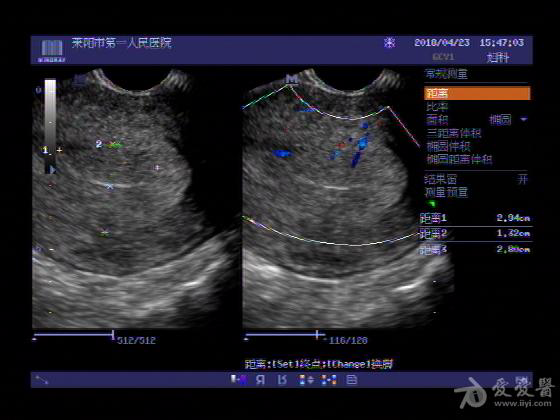

女,48岁,月经量多,两个月,一年前出现过类似现象,刮宫吃药后缓解。

超声可见:子宫内膜显著增厚,后肌壁内膜可见范围约3.27X0.90CM低回声区,CDFI显示较丰富线样血流,宫底宫腔内见类**状低回声结节。前肌壁见多发类圆形低回声结节。

超声提示:子宫内膜增厚(建议刮宫病理),子宫多发肌瘤

病理结果:内膜增生